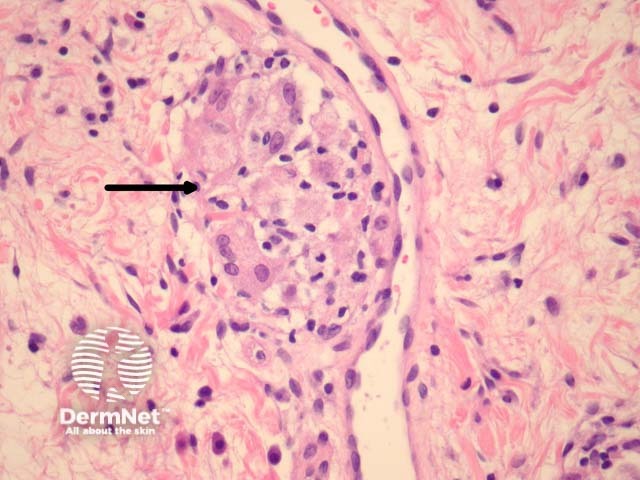

In orofacial granulomatosis, sections show oral mucosa with a sparse inflammatory infiltrate and mild oedema (figure 1). Higher power examination shows ectasia of lymphatics next to rare loose granulomas (figures 2-4, arrows indicate granulomas). Sometimes the granulomas may be difficult to find and extensive serial sectioning of the biopsy is recommended.

Figure 2